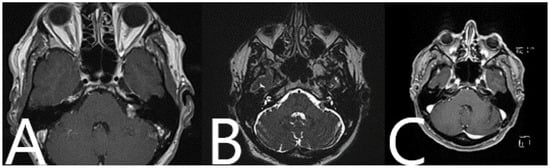

| Patient Characteristics | Non-AR Group | AR Group |

|---|---|---|

| Number of patients | 27 | 16 |

| Age | 65.11 years | 51.21 years |

| Gender | Male 12 Female 15 | Male 6 Female 10 |

| Hannover classification | T2 6 T3a 3 T3b 5 T4a 6 T4b 7 | T2 3 T3a 2 T3b 4 T4a 1 T4b 6 |

| Extent of resection | 1 TR 15 GTR 11 STR | 9 GTR 7 STR |

| Positioning | Sitting position 11 Semi-sitting position 16 | Sitting position 16 |

| Operative time | 320 ± 86.4 min | 310 ± 109.3 min |

| Hospital stay | 11.7 ± 6.6 days | 9 ± 4.2 days |

| Complication rate | 9/27 patients Patient Nos. 2, 3, 17, 22, 25, 27—CSF leak with wound healing deficit Patient Nos. 1, 14, 25 and 27—shunt-dependent hydrocephalus Patient No. 11—pneumothorax | 4/16 patients Patient Nos. 33, 42—CSF leak, wound healing deficit Patient No. 39—CSF leak, wound healing deficit, shunt dependent hydrocephalus Patient No. 34—postoperative contralateral supratentorial subdural hematoma |

| Preoperative CN VII function (HB grade) | 22 HB I 3 HB II 1 HB IV 1 HB V | 15 HB I 1 HB IV |

| Postoperative CN VII function (HB grade) | 12 HB I 6 HB II 1 HB III 4 HB IV 4 HB V | 7 HB I 2 HB II 2 HB III 5 HB IV |

| Postoperative CN VII function unchanged/worsened | 16 unchanged 11 worsened | 8 unchanged 8 worsened |